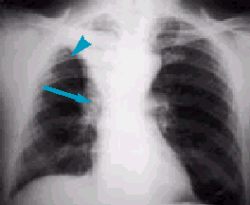

На рентгеновских снимках выявляют следующие признаки, указывающие на спадение легочной ткани:

Однородное затемнение в области поражения. Размеры тени зависят от вида ателектаза: при долевом выявляется обширное затемнение, при сегментарном — в виде клина или треугольника, расположенного вершиной к корню легкого, дольковые ателектазы множественные и похожи на очаговую пневмонию. Дистензионный ателектаз расположен низко, около диафрагмы, имеет небольшие размеры и вид поперечных полос или темных дисков. Смещение органов: при компрессионном ателектазе смещение наблюдается в здоровую сторону, так как на стороне поражения давление больше, при обтурационном, наоборот – смещение будет в сторону ателектаза, так как на стороне поражения нарастает притягивающее отрицательное давление. Подъем купола диафрагмы – это видно по расположению печени.

Помимо всего перечисленного выше, рентгеноскопия, то есть исследование «вживую», позволяет увидеть куда смещаются органы в зависимости от фазы дыхания, кашля. Это является дополнительным признаком ателектаза, помогающим выявить тип болезни.

- дисковидный ателектаз – развивается на фоне сжатия нескольких долек лёгкого;

- линейный ателектаз.